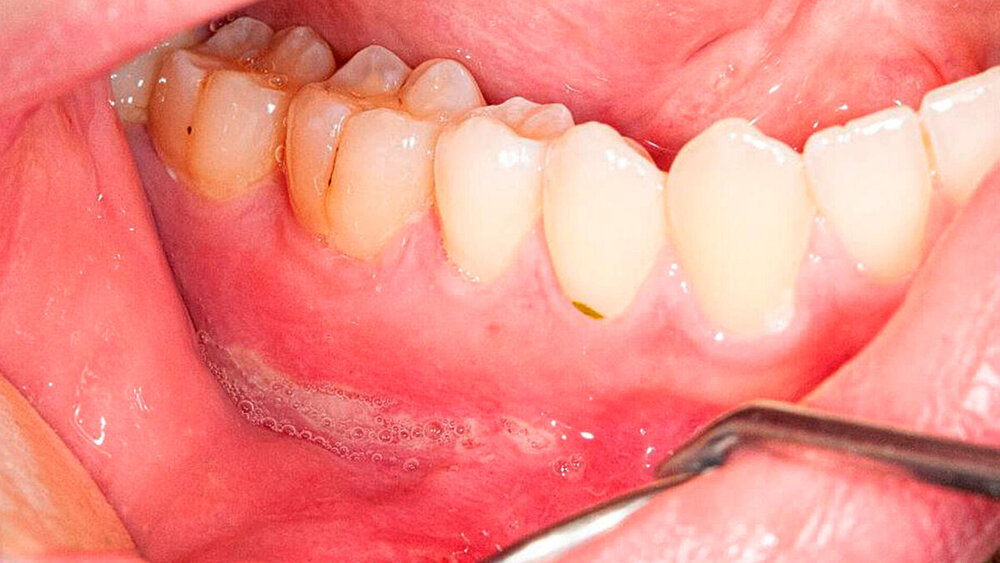

In der klinischen Untersuchung zeigte sich im Bereich der Umschlagfalte des Unterkiefervestibulums auf beiden Seiten jeweils eine langstreckige ulzeröse Schleimhautveränderung. Auf der linken Seite war die Veränderung deutlich stärker ausgeprägt als rechts. Rechts reichte die circa 4 cm x 0,5 cm messende, ulzeröse Läsion von regio 34 bis in regio 38, zentral mit stark mazeriertem Gewebe und Verlust der Oberflächenintegrität. In der Tiefe ließ sich bis auf das darunter liegende Periost sondieren, es zeigte sich kein freiliegendes Os. Rechts zeigte sich ein weniger eindrucksvolles Bild durch eine deutlich oberflächlichere und kleinere Fibrin-belegte Läsion (Abbildungen 1 und 2). Die Veränderungen im Bereich der Umschlagfalten tasteten sich weich, ohne indurierten Randwall. Es zeigte sich kein Austritt von Pus, und auch keine nennenswerte Schwellung. Die beiden Ulzera waren auf Palpation schmerzhaft. Die restliche Mund- und Rachenschleimhaut erschien – soweit einsehbar – reizlos und intakt. Die Mundhygiene des Patienten erschien adäquat, bei einem konservierend versorgten Gebiss. In der angefertigten Panoramaschichtaufnahme ergaben sich kein morphologisches Korrelat und kein dentogener Fokus für die beiden schmerzhaften Läsionen (Abbildung 3).

Ein halbes Jahr nach Beginn der Systemtherapie stellte sich der Patient in unserer Hochschulambulanz zur Verlaufskontrolle vor. Der junge Mann befand sich in einem deutlich gebesserten Allgemeinzustand. Zu den vorbekannten gastrointestinalen Beschwerden sei es seit der Therapieeinleitung kaum noch gekommen. Die Läsionen der Mundschleimhaut sind dem Patienten zufolge bereits nach der zweiten Gabe des TNF-Blockers vollständig abgeklungen und seither nicht mehr aufgetreten. Auch zu Schmerzen im Bereich der Mundschleimhaut sei es seither nicht mehr gekommen. Im klinischen Befund bei der Verlaufskontrolle zeigte sich eine reizlose und intakte Mundschleimhaut und die beiden Initialläsionen waren vollständig ausgeheilt (Abbildungen 5 und 6). Die Systemtherapie wird bisher ohne Nebenwirkungen vertragen und es erfolgt weiterhin eine engmaschige internistische Anbindung.